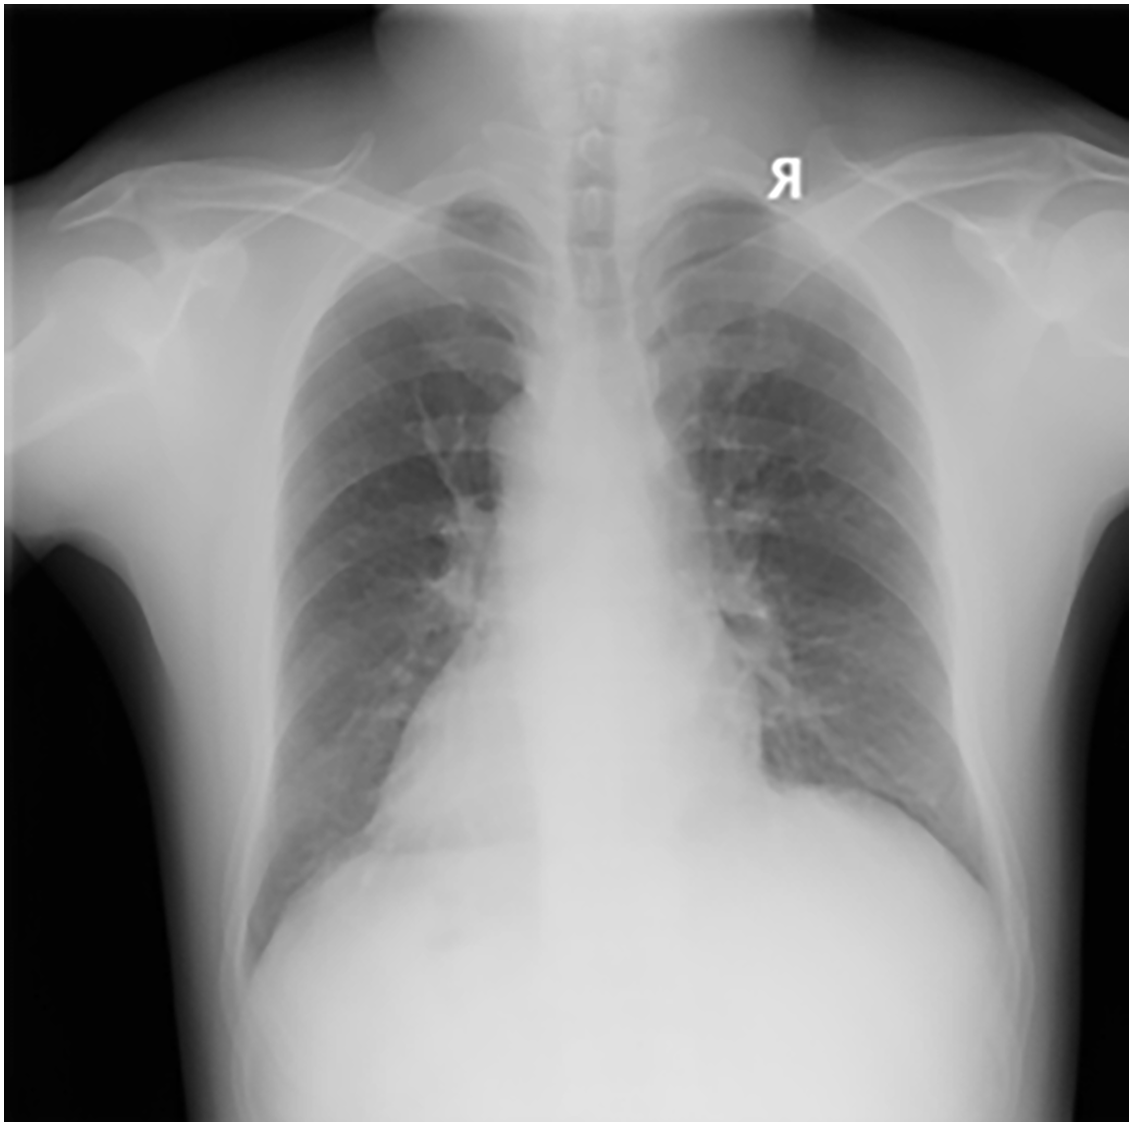

The dataset used in this study was collected by the Occupational Disease Prevention Hospital of the Tongmei Group from 2020 to 2021, covering DR high-voltage imaging data of a total of 934 patients. All chest X-ray data were obtained from outpatients, inpatients, and occupational health screening populations. Among them, there were 256 cases of stage 0 pneumoconiosis, 545 cases of stage 1 pneumoconiosis, 86 cases of stage 2 pneumoconiosis, 28 cases of stage 3 pneumoconiosis, and 19 cases of stage 3+ pneumoconiosis, as shown in Table 1. As shown in Fig. 1, a DR image of a pneumoconiosis patient is presented.

Figure 1: DR image of a pneumoconiosis patient